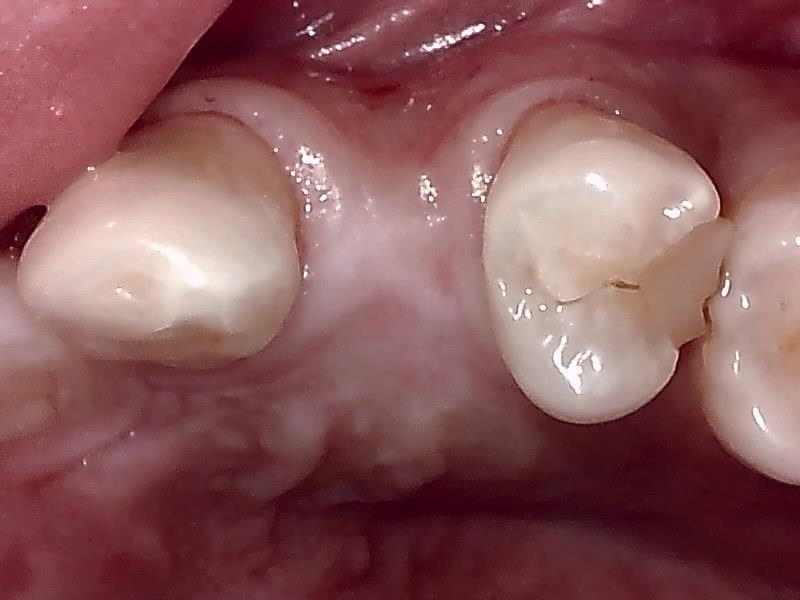

術前の顎堤

術前の時は瘦せていた顎堤が適切なグラフト手技により

しっかりした厚みのある顎堤が隆起している。

インプラント埋入後、10ヶ月経過した健全な顎堤の状態です。